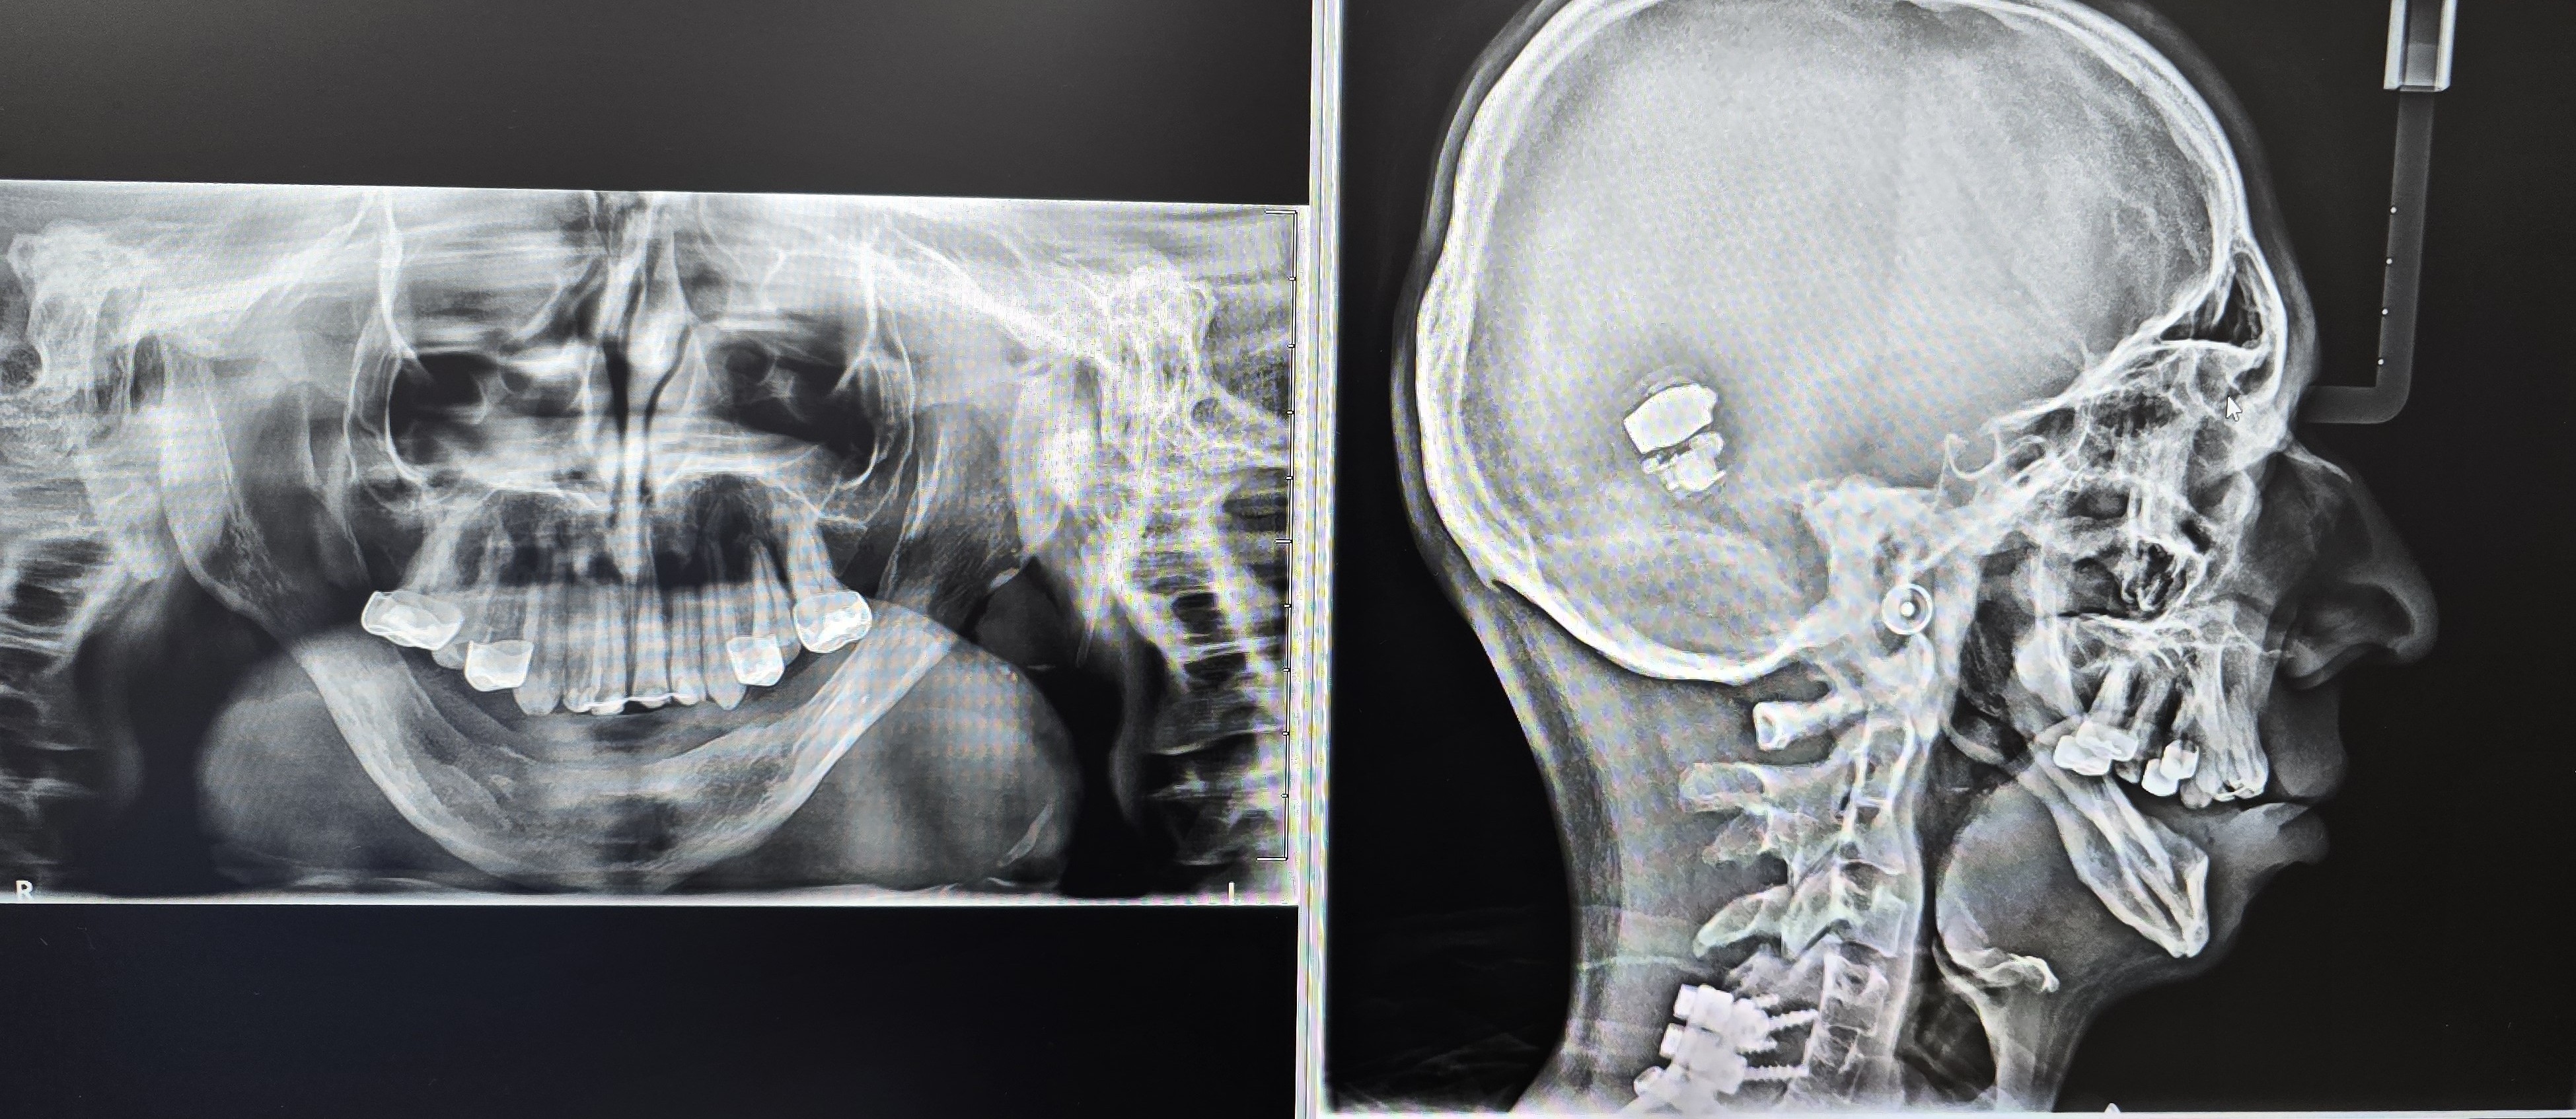

He originally underwent bilateral mandibular DO at the age of two years for airway obstruction. Persistent mandibular hypoplasia into adulthood required a repeat DO at age 19, achieving approximately 18-23 mm advancement at 1 mm/day. As reported in syndromic craniofacial literature, long-term mandibular form after distraction can remain suboptimal due to altered growth vectors and limited intrinsic regenerative capacity [6-8, 15]. Postoperative imaging demonstrated inadequate mandibular width and incomplete consolidation (Fig 1).

Following his second DO and due to persistent a thin mandibular alveolar ridge, bone morphogenetic protein (BMP)-augmented allograft reconstruction was attempted about half a year later but failed to generate sufficient bone volume. This finding is consistent with reports of variable graft success in congenital mandibular deficiency [16]. Given two prior distraction attempts, graft failure, and the morbidity associated with fibula free-flap mandibular reconstruction, a CAD-CAM titanium subperiosteal implant was selected as definitive treatment. Patient has agreed to the proposed treatment and has signed consent form also for documentation and publication of his case.